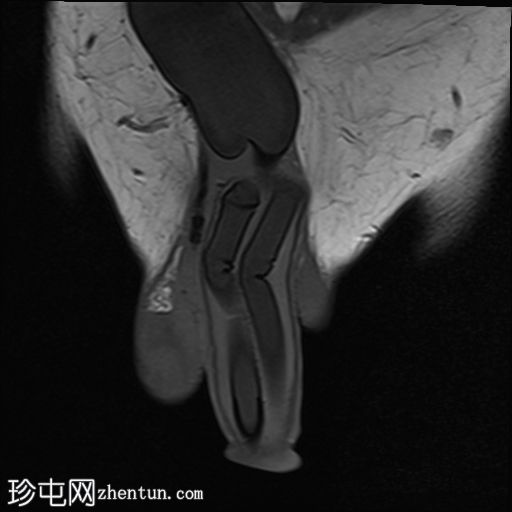

冠状位

STIR序列

MRI显示可充气式阴茎假体位于体内。

假体柱体对称地位于阴茎海绵体内,并沿其走行方向完全扩张。

未见海绵体破裂或假体柱体断裂的迹象。

泵储液囊位于阴囊内,位置正常。

阴囊壁皮下可见轻度水肿,但无明显积液,可能为反应性水肿。

储液囊位于右侧腹股沟管前方的皮下脂肪内,对右侧腹直肌施加轻微的向上压迫,周围有少量积液。这些发现最符合术后改变。

在本病例中,MRI显示假体圆柱体位置正常,无破裂或不连续的迹象。储液囊和泵的位置也正确。周围轻微的水肿和积液可能是术后改变。因此,患者的症状可能与机械刺激或装置相关的机械因素有关,而不是假体的结构性故障。